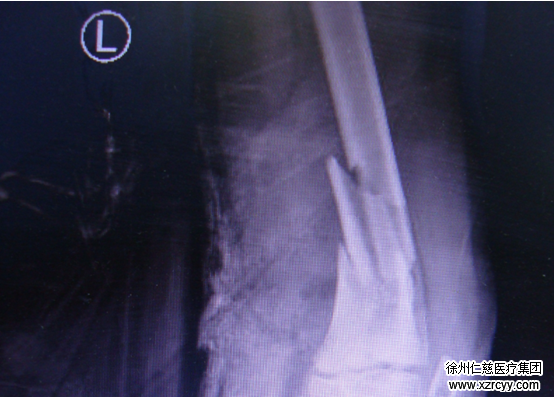

圖一:術(shù)前檢查

3月26日上午,安徽宿州的一名9歲男孩,不慎啟動了停在路邊的電動三輪車。不受控制的車輛撞到樹上傾翻,重重的砸到孩子腿上,致其左腿腘動脈及神經(jīng)斷裂。因當(dāng)?shù)蒯t(yī)療條件有限,簡單包扎后孩子被送至徐州仁慈醫(yī)院。待收治入院時,已休克。

回憶起接診時的情景,小志的主治大夫黎醫(yī)生介紹說“送來的時候,孩子已休克。左足背動脈、脛后動脈搏動消失,各足趾蒼白、毛細(xì)血管反應(yīng)消失”醫(yī)護(hù)人員迅速反應(yīng),以最快的速度,將小志送往手術(shù)室。

“你看這個圖”黎醫(yī)生指著傷口的照片(圖二)說“股骨下端粉碎性骨折累及骨骺,腘動脈及伴行靜脈完全栓塞,長約3cm,腓總神經(jīng)、脛神經(jīng)各斷裂約1/4,股二頭肌長頭、腓腸肌、半腱肌、腘肌、跖肌各斷裂約1/3。”從血肉模糊的照片中,很直觀便能看到當(dāng)時的嚴(yán)重程度。